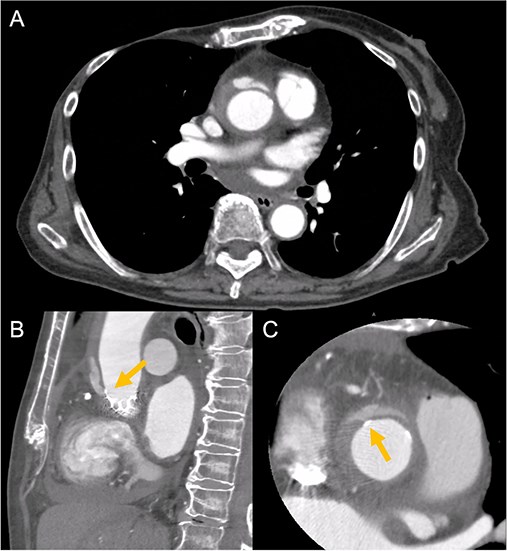

Contrast-enhanced CT on day 7 after discharge shows an AAD in the ascending aorta (A) with the entry point at the STJ extending toward the THV stent frame, suggesting an AAD associated with TAVI (B and C, arrow).

An 88-year-old woman with severe symptomatic AS (aortic valve area: 0.40 cm2; peak velocity: 4.9 m/s; mean pressure gradient: 56 mm Hg) and ischemic heart disease with severe stenosis in the proximal segments of both the left anterior descending (LAD) coronary artery and circumflex arteries was referred from another hospital for invasive treatment. The patient was taking edoxaban 30 mg, nifedipine 20 mg, perindopril 4 mg, and candesartan 8 mg for the treatment of atrial fibrillation and hypertension. The patient’s perioperative risk was high, with a Society of Thoracic Surgeon (STS) score of 9.31% and Logistic EuroSCORE of 23.11%. Following discussion with the heart team, we decided to perform TAVI before coronary revascularization, with percutaneous coronary intervention (PCI) planned postoperatively. We evaluated the aortic valve complex using contrast-enhanced computed tomography (CT), which revealed a narrow sinotubular junction (STJ) with small calcifications measuring 20.6 × 22.3 mm (Fig. 1). TAVI was performed via a transfemoral approach under local anesthesia and sedation. A 23-mm SAPIEN 3 THV (Edwards Lifesciences, Irvine, CA, USA), which provides better coronary access due to its shorter frame length and relatively larger cell size, was deployed without prior balloon aortic valvuloplasty. To minimize the risk of injury to the STJ, the THV was deployed with a reduced balloon volume (−1 cc), and post-dilatation was conducted with the balloon positioned toward the left ventricular side (Fig. 2). Postoperatively, the patient’s blood pressure stabilized with rest and a reduced-sodium diet, allowing modification of the antihypertensive therapy to sacubitril/valsartan 100 mg alone. Additionally, aspirin 100 mg was added to ongoing edoxaban therapy for the planned PCI. The postoperative course was uneventful, and the patient was subsequently discharged. However, on day 4 after discharge, the patient experienced acute chest discomfort. Blood tests, electrocardiography, and transthoracic echocardiography revealed no significant changes from the time of discharge, and the patient was sent home as the symptoms gradually improved. On day 7 after discharge, contrast-enhanced CT—originally scheduled as a preoperative assessment for PCI at the referring hospital— incidentally revealed a localized dissection of the ascending aorta. The entry point of the dissection was located at the STJ extending toward the THV stent frame, consistent with Stanford AAD associated with TAVI (Fig. 3). The patient was transferred to our hospital and underwent surgery, including aortic valve replacement, ascending aorta replacement, and coronary artery bypass grafting (left internal thoracic artery to the LAD and saphenous vein graft to the obtuse marginal branch). Intraoperatively, removal of the THV and calcified STJ tissue revealed a pinhole-like intimal defect, which was continuous with a hematoma within the media and identified as the entry point of the dissection. Macroscopic pathological examination of the resected ascending aorta also confirmed the presence of a small intimal defect (Fig. 4). This intimal injury was therefore considered to have resulted from compression of the calcified tissue caused by THV implantation. After ~1 month of rehabilitation, the patient was discharged in an ambulatory state on postoperative day 30.